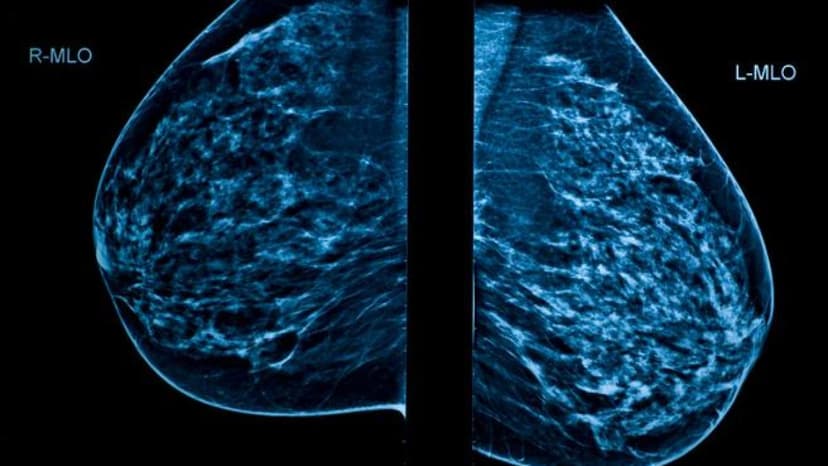

With belligerence and a combative spirit, we can face illness. Especially if we understand its image.